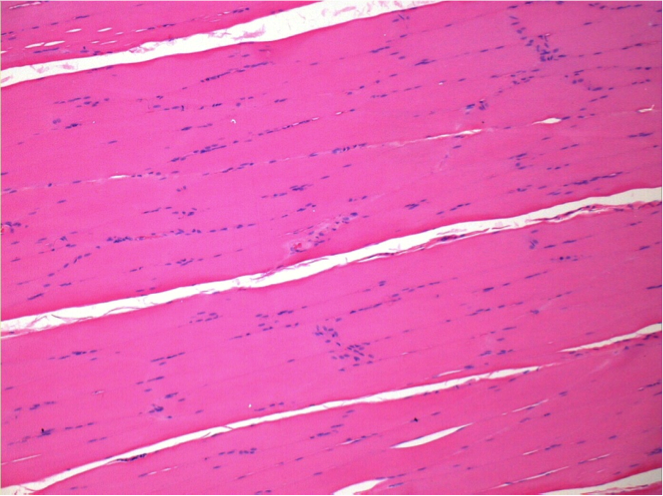

Control

Comentario: Nada que declarar después de la inyección de solución salina.

L: Pretibial-Sin tratamiento

R: Pretibial-Después de 0,1 ml de NaCl 0,9% IM